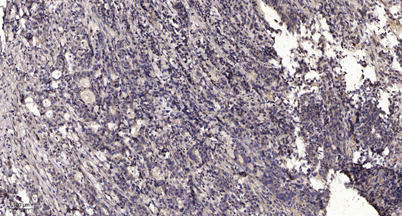

Applications’╝ÜWB;ELISA;IHC

Õģ│µ│©ÕŠ«õ┐ĪÕģ¼õ╝ŚÕÅĘ

ÕŠ«õ┐Īµē½õĖƵē½Ķ┐×Õ┐ÖÕÆ©Ķ»ó

ÕŠ«õ┐Īµē½õĖƵē½Ķ┐×Õ┐ÖÕÆ©Ķ»ó